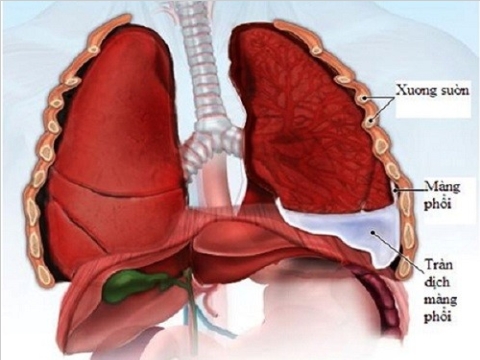

- Tràn dịch màng phổi không rõ nguyên nhân.